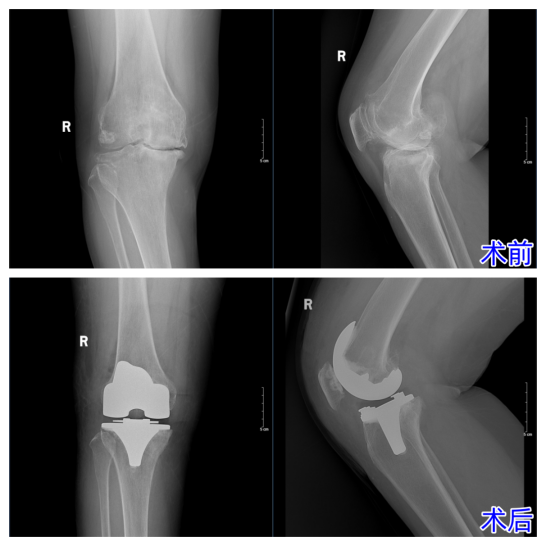

面对这位典型的疑难病例,杨主任团队没有丝毫懈怠。经过缜密的术前评估与个性化方案制定,杨主任亲自操刀,凭借对解剖结构的精准把控与炉火纯青的技术,成功实施了膝关节置换术。术中,病变组织被精准清除,畸形得以矫正,人工关节精准复位。

术后,在医护团队的悉心照料下,王女士迎来了奇迹般的转变。膝关节的僵硬感消失,活动度大幅提升,变形的腿部恢复了正常力线。这场手术,不仅仅置换了一个关节,更置换回了王女士对生活的热爱与尊严。